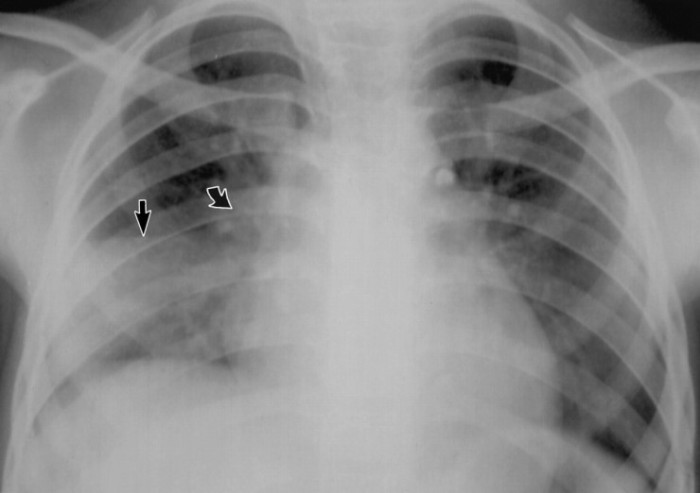

4. 폐결핵

헌종과 철종이 폐결핵으로 사망했다.

특히 헌종의 경우 후궁들과 무리한 정사를 벌이다 폐결핵에 걸렸다고 알려졌다.